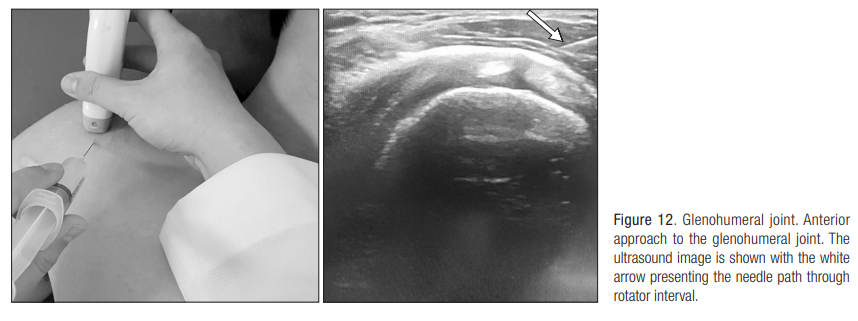

7. 견관절 관절강내 주사( Glenohumeral joint injection)

어깨 관절 내로 주사를 하는 방법이다.

견관절의 유착성 관절낭염(오십견)은 관절의 움직임이 제한되고, 통증을 유발하는 질환

이때 스테로이드제와 증식요법제를 작용하면 통증과 관절 운동을 호전시킬 수 있다

관절 내 스테로이드 주사는 초기에 사용시 6주 이내에 통증이 없도록 회복

동결기 에서는 야간통과 휴식 시 발생하는 통증을 줄임.

따라서 오십견의 자연 경과를 짧게 하는 효과를 발휘한다.

주사 자세: 후방 및 전방에서 모두 접근 가능

1) 후방에서 접근:

Posterior labrum과 Humeral head 사이를 목표로 needle을 위치

탐촉자의 lateral에서 medial 방향으로 in-plane으로 삽입

2) 전방에서 접근

: rotator interval을 통해서 접근, 누운 자세에서 시행

: 외측에서 내측으로 접근, SS와 SC 사이 및 CHL 아래에 있는 구획으로 needling